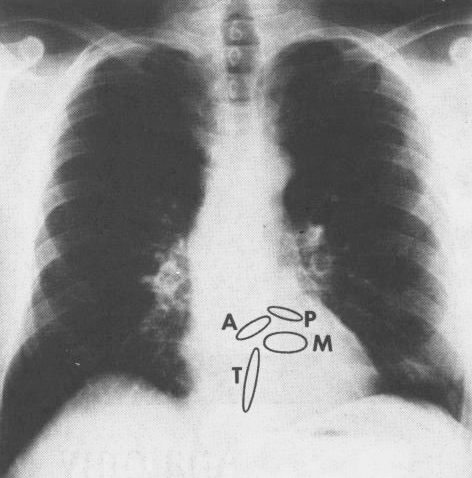

Anatomy Of The Heart

Tavr Faq S Answered By A Cardiologist Myheart Net